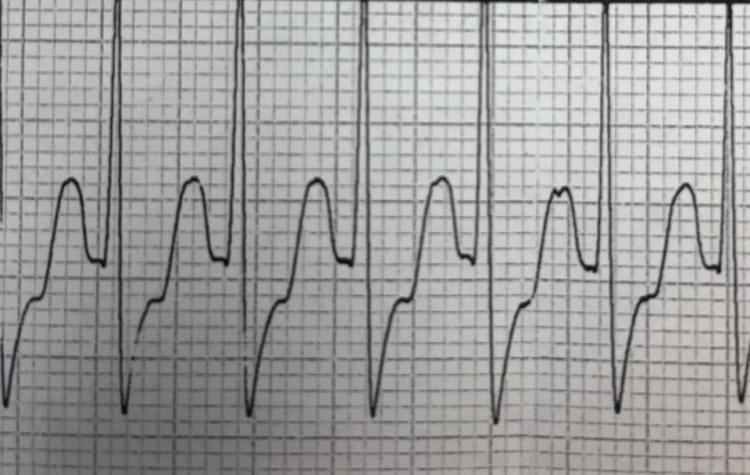

Differentiation of SVT from Sinus Tachycardia

SVT is an umbrella term

Undifferentiated tachycardia via ems12lead.com